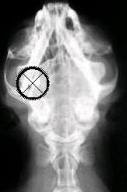

Um gato sobreviveu após ter levado um tiro de chumbinho no cérebro. Foi à segunda vez que o felino foi alvo de crueldade nos últimos dois anos, segundo o jornal britânico "Lancashire Telegraph". Em 2007, o gato chamado "Bobby" foi alvejado na perna e precisou passar por uma cirurgia para retirar o projétil. Ele tinha se recuperado bem, mas a proprietária do animal, a britânica Susan Stone, ficou horrorizada na última quinta-feira, quando encontrou seu bicho de estimação coberto de sangue. Dessa vez, ele tinha levado um tiro de chumbinho na cabeça. Susan Stone levou "Bobby" a uma clínica veterinária, onde ele fez um raio-X. O exame mostrou que o chumbinho continuava no crânio do gato, atrás de seu olho direito. Devido à localização, as tentativas de retirar o projétil por cirurgia fracassaram. O veterinário acabou optando por limpar o ferimento e costurá-lo, deixando o chumbinho no lugar. Para Susan, que gastou 500 libras no tratamento, o fato de seu animal de estimação ter sobrevivido é um "milagre". Ela se declarou indignada com o fato e acredita que a pessoa que praticou a maldade foi à mesma da vez anterior. Um amigo de Suzan brincou dizendo que ela deveria providenciar um ‘colete a prova de balas’ para o seu bichano.